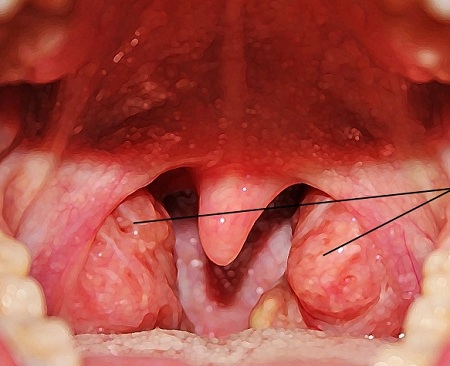

Как проводится операция?

Операция проводится в несколько этапов:

- Анестезирование. Как правило, используется общий наркоз. Его выбор будет осуществлять опытный анестезиолог с учётом особенностей организма пациента.

- Затем будет проведено удаление миндалин. На это уходит в среднем 30-60 минут.

- Затем действие наркоза закончится, и пациент начнёт приходить в себя.

Процедура удаления миндалин